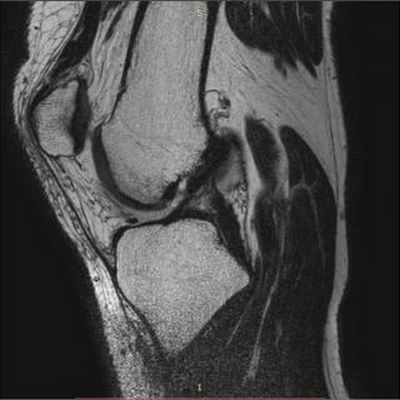

(Левый) При МРТ в сагиттальной плоскости на Т1ВИ определяется нарушение целостности верхнемедиального пучка подошвенной пяточно-ладьевидной связки. Оценивать связку следует во всех трех плоскостях, чтобы исключить эффект частичного объема.

(Правый) У этого же пациента при МРТ в сагиттальной плоскости в режиме STIR подтверждается разрыв верхнемедиального пучка подошвенной пяточно-ладьевидной связки она растянута и утолщена. Отек костного мозга в головке таранной кости обусловлен отсутствием ее поддержки подошвенной пяточно-ладьевидной связкой и нарушением биомеханики движения. (Левый) У этого же пациента при МРТ в коронарной плоскости на ППВИ определяется гетерогенная структура утолщенного подошвенного пучка подошвенной пяточно-ладьевидной связки. Вблизи выявляется нечеткий контур разорванной большеберцово-пяточно-ладьевидной связки Сухожилие задней большеберцовой мышцы окружено аморфным мягкотканным субстратом.

(Правый) У этого же пациента при МРТ в коронарной плоскости на Т2ВИ в режиме FS визуализируется дефекта между волокнами подошвенной пяточно-ладьевидной и больше-берцово-пяточно-ладьевидной связок. Также выявляется выраженный тендовагинит задней большеберцовой мышцы. (Левый) При МРТ в аксиальной плоскости на ППВИ в режиме FS определяется интактный продольный нижний подошвенный пучок подошвенной пяточно-ладьевидной связки. Медиально выявляется скопление жидкости, обусловленное разрывом верхнемедиального пучкам.

(Правый) У этого же пациента при МРТ в аксиальной плоскости на ППВИ в режиме FS на срезе, проходящем чуть выше, визуализируется разрыв большеберцово-ладьевидного и большеберцово-пяточно-ладьевидного пучков поверхностного слоя дельтовидной связки. Также выявляется тендинопатия задней большеберцовой мышцы.

3. МРТ повреждения подошвенной пяточно-ладьевидной связки:

• При разрыве связка выглядит растянутой, волнистой либо прерывается

• В случае ретракции культя связки может утолщаться

• Подтвердить разрыв связки бывает достаточно трудно:

о Часто стопа находится в положении пронации, вследствие чего изменяется ход связки

о Следует тщательно сопоставлять выявленные в разных плоскостях патологические изменения